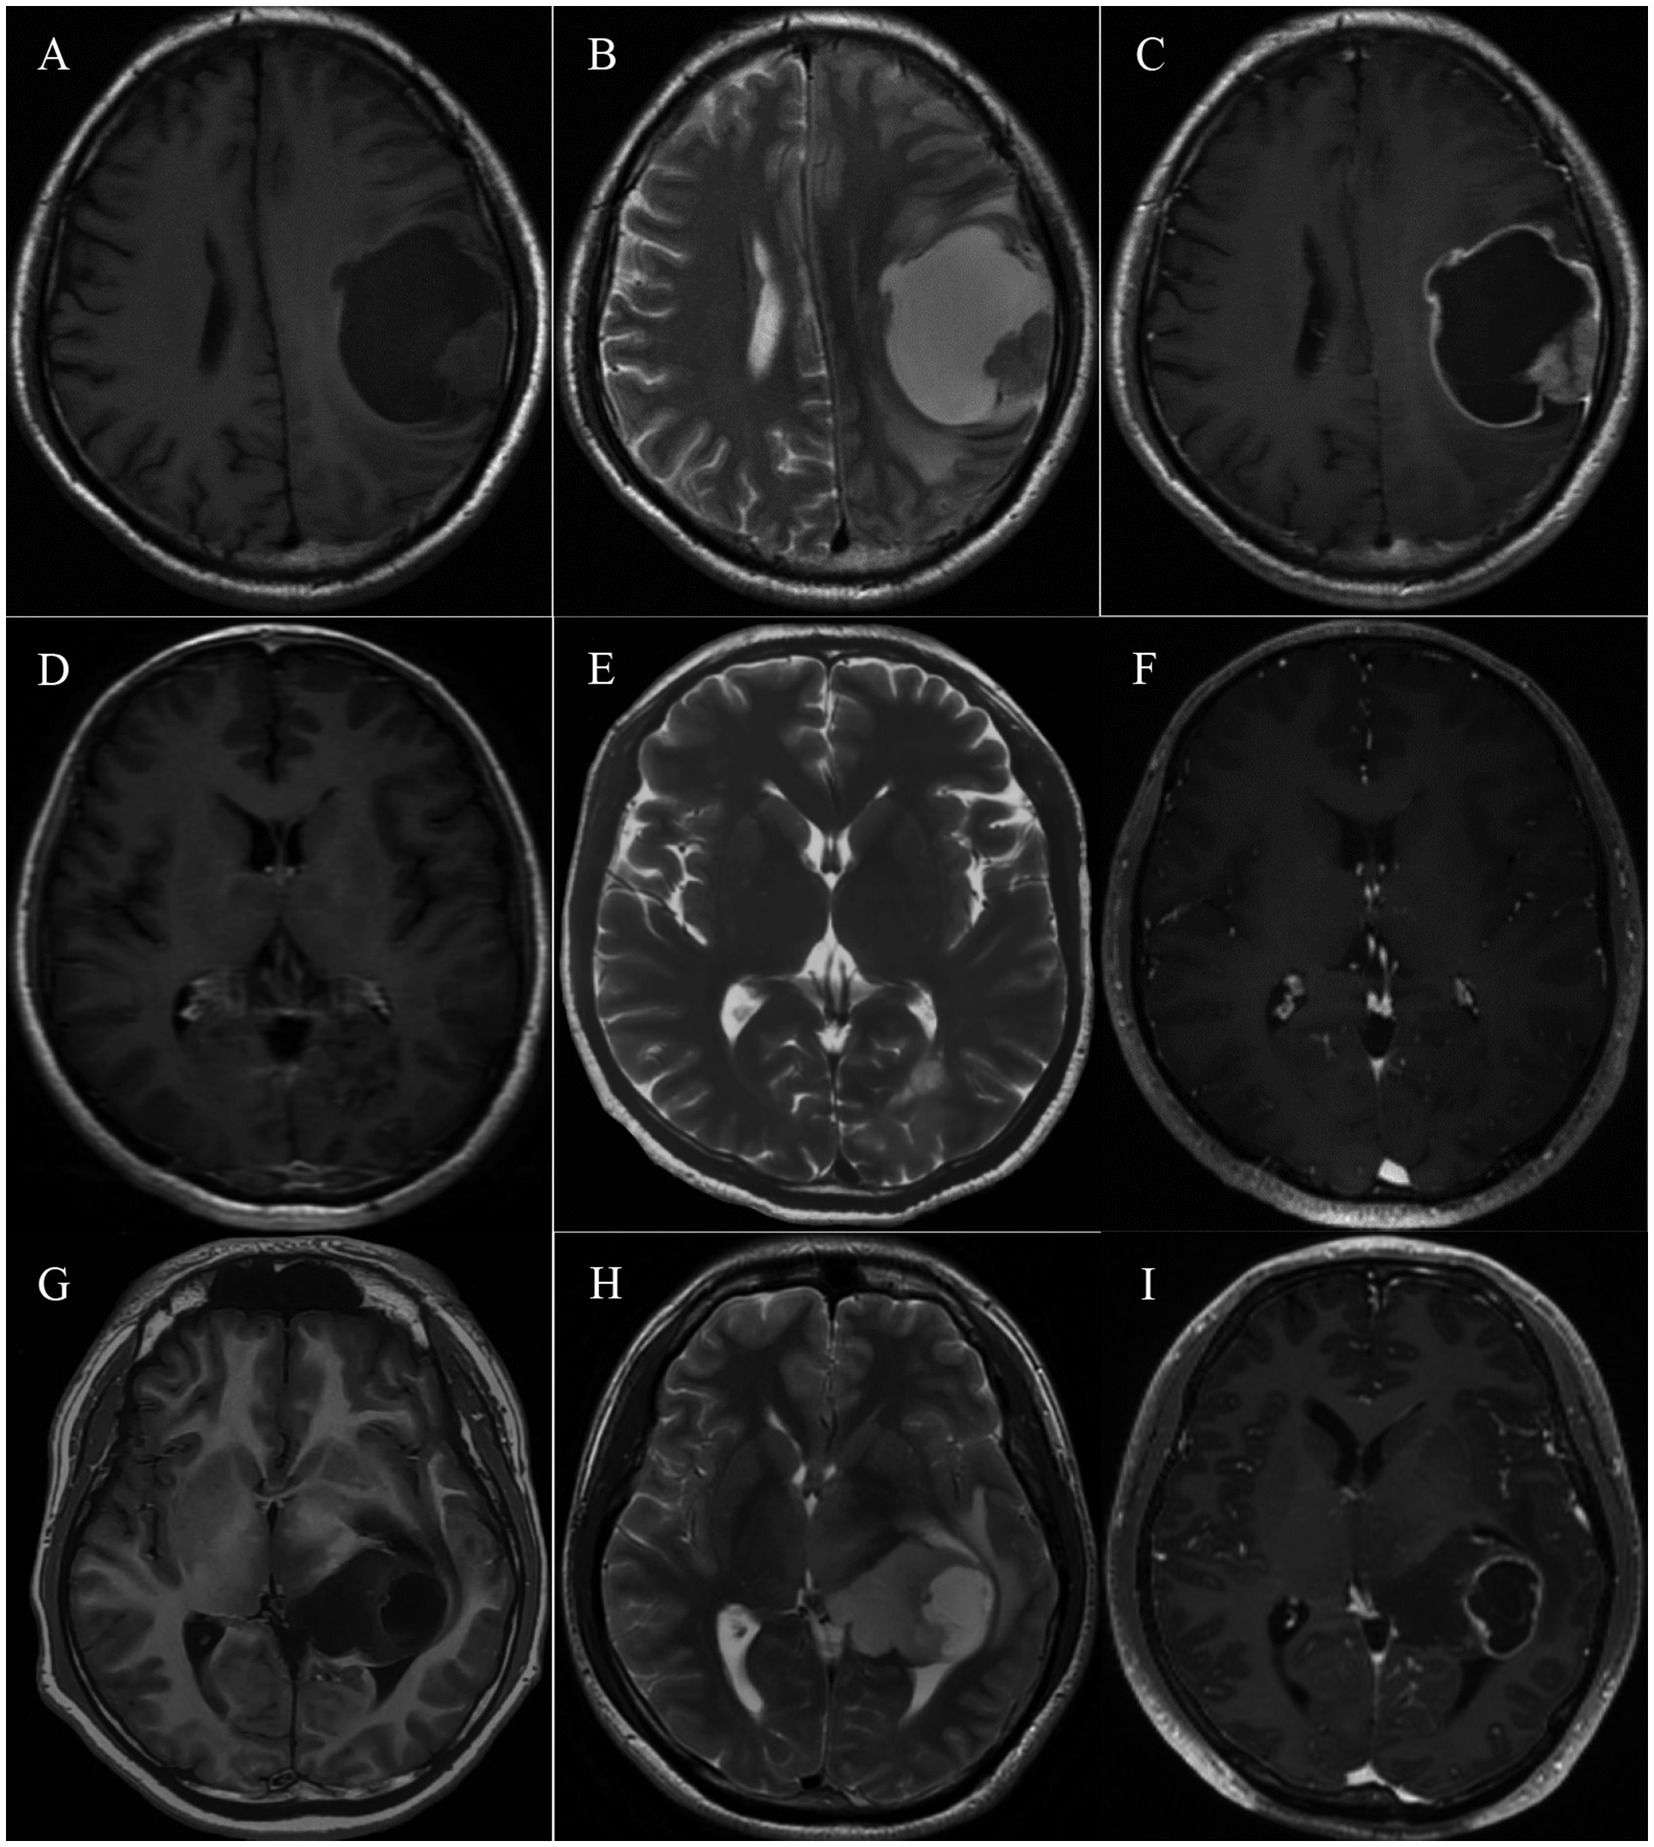

Глиомы — это агрессивные и, увы, неизлечимые раковые опухоли мозга, известные своим особым иммуносупрессивным окружением, насыщенным миелоидными клетками. Именно эти клетки играют ключевую роль в формировании условий, которые мешают иммунной системе бороться с опухолью. Ученые долгое время пытались разгадать загадку этих клеток, ведь понимание их функций открывает путь к созданию новых методов лечения.